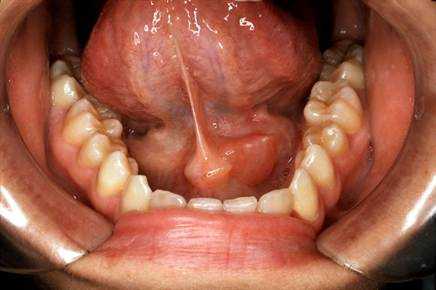

Киста - это капсула, заполненная жидким содержимым, которая возникает на месте слюнной железы. Для кисты характерны те же проявления, что и для закупорки протока слюнной железы. Характерной особенностью кист слюнных желез является тенденция к прогрессирующему росту.

Калькулезный сиаладенит — заболевание, связанное с закупоркой протоков слюнных желез камнем;

Кисты слюнных желез — опухолеподобные образования, возникающие в результате нарушения проходимости выводных протоков после травмы или воспалительных процессов;